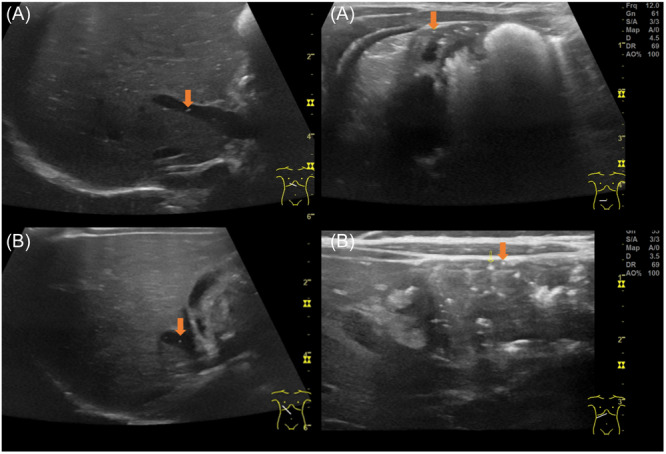

Bloody stools are a particularly concerning symptom in neonates and infants. The differential diagnosis reaches from life-threatening to benign conditions. We would like to present two infants, who presented to the paediatric emergency department with bloody stools and showed pneumatosis on ultrasonography, which initially led to the suspicion of a potentially life-threatening condition. Both children had an unremarkable physical examination and both the laboratory chemical parameters, as well as the stool analyses were without abnormal findings. As in summary, there was no evidence of necrotizing enterocolitis, and Food Protein-Induced Allergic Proctocolitis (FPIAP) was considered the most likely diagnosis, an ambulant nutritional counselling was provided. As FPIAP is a clinical diagnosis, the number of cases in which pneumatosis can be detected is unclear. It is speculated that, like atopic dermatitis, food allergies alter, for example, the tight junctions and lead to an increased intestinal permeability which might result in pneumatosis intestinalis.